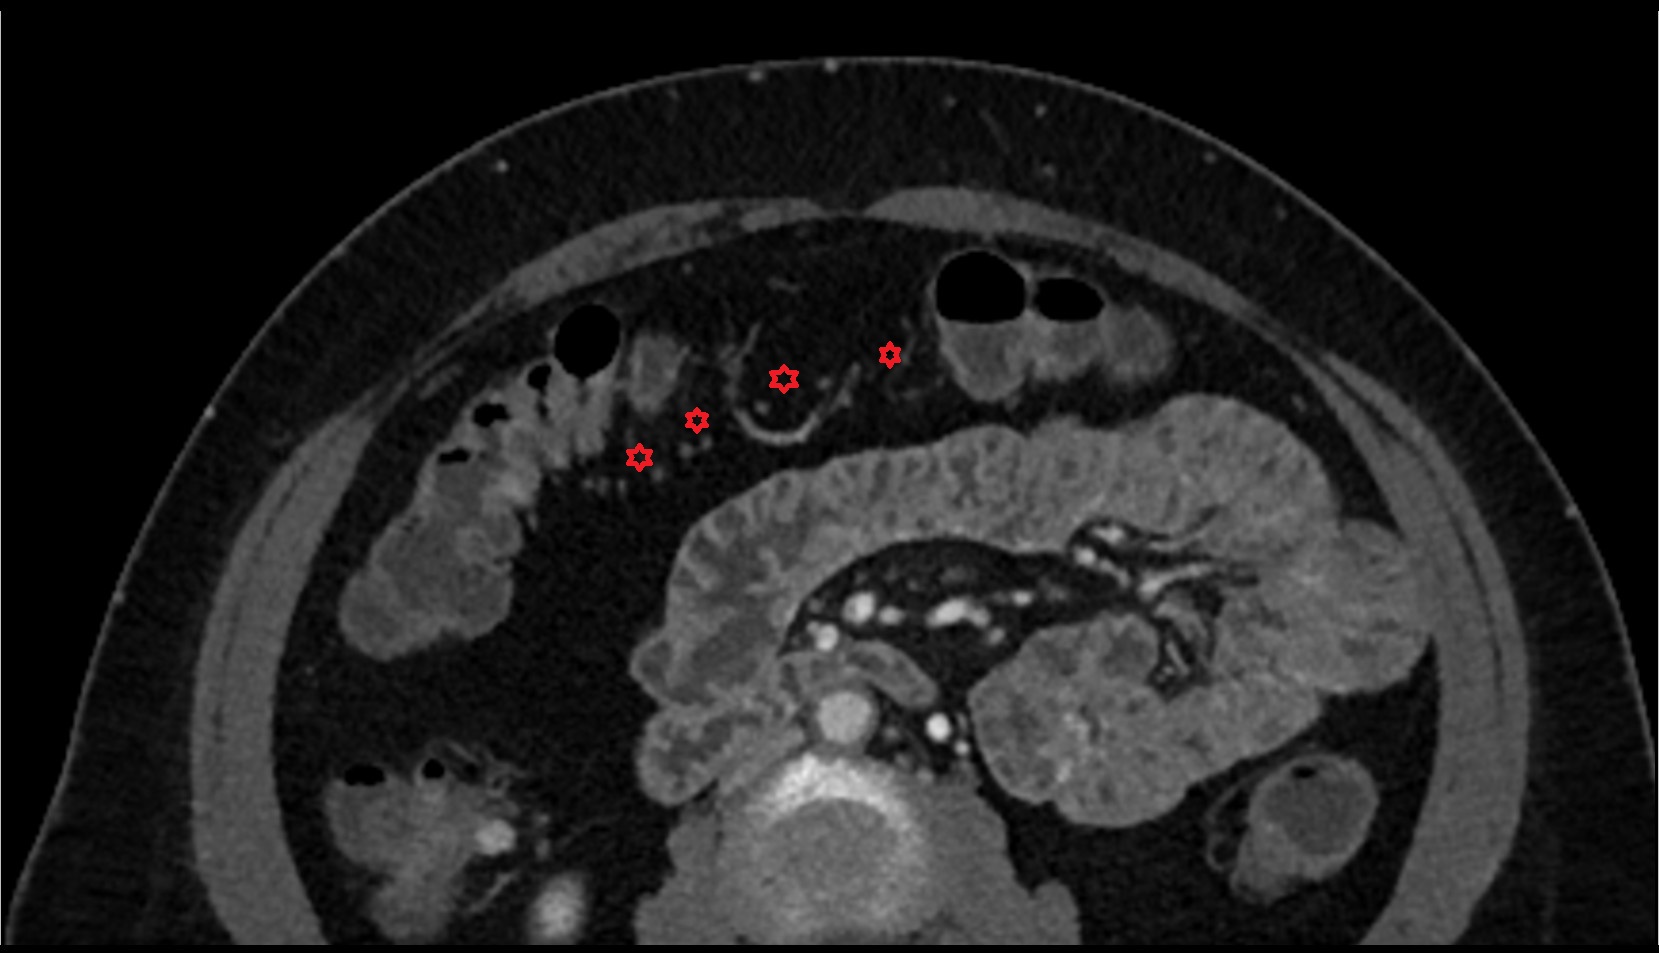

- Maternal ovaries

- Ovaries

- Right ovary

- Left ovary